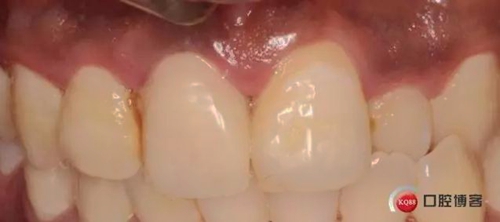

兩月后牙齦恢復(fù)正常穩(wěn)定。正式取模,E.max鑄瓷修復(fù)

可以看出牙齦袖口很漂亮,修復(fù)體外形也不錯(cuò),就是顏色偏白一點(diǎn),讓患者改色,患者覺得已經(jīng)很滿意了,而且考慮其他牙以后做美白,所以不換了。

可以看出修復(fù)體的邊緣密合度都很好。希望這次修復(fù)能夠讓這顆牙多服役幾年吧